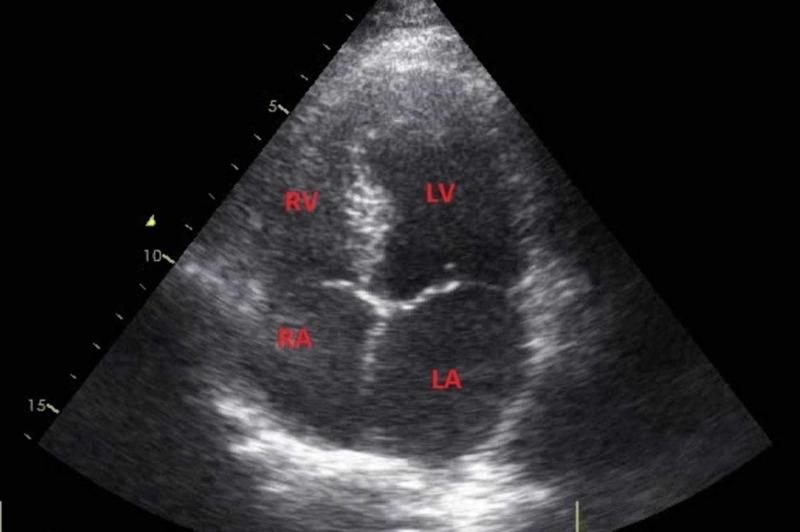

The risk of stroke is increased during pregnancy and the postpartum period. It can lead to significant maternal morbidity and mortality. The physiologically mediated hemodynamic changes in circulation and vascular tissue, and the increased coagulability account for this increased risk of stroke. Pregnancy-related strokes can be hemorrhagic or ischemic. We present a rare case of postpartum ischemic stroke. A 25-year-old female with no known comorbidities and a history of cesarean section 10 days back presented with a right-sided weakness and sensory loss for one day. An MRI of the head revealed a large area of restricted diffusion on diffusion-weighted 1 (DW1) image in the left parietal region with comparable low signals on apparent diffusion coefficient (ADC) map and a small area of blooming suggesting hemorrhage on susceptibility-weighted 1 (SW1) image. This area appeared hypointense on T1 and hyperintense on fluid-attenuated inversion recovery (FLAIR) and T2 images. These findings suggested acute ischemic infarction. She was started on antiplatelet therapy, and subsequently, her weakness improved. She was discharged upon improvement in her symptoms and was asked to follow up in the outpatient department. Numerous studies have shown an increased risk of ischemic stroke in the immediate postpartum period in women who undergo a cesarean section. Thus, we conclude that clinicians should be aware of this complication and high-risk patients should be identified and monitored more aggressively in their immediate postpartum period.

在孕期和产后期间,中风风险会增加。它可导致严重的孕产妇发病和死亡。循环系统和血管组织中生理介导的血流动力学变化以及凝血性增加是中风风险增加的原因。与妊娠相关的中风可以是出血性的或缺血性的。我们报告一例罕见的产后缺血性中风病例。一名25岁女性,无已知合并症,10天前有剖宫产史,出现右侧肢体无力和感觉丧失1天。头部MRI显示左侧顶叶区域在扩散加权1(DW1)图像上有大面积扩散受限,在表观扩散系数(ADC)图上有类似的低信号,在磁敏感加权1(SW1)图像上有一小片提示出血的高信号影。该区域在T1加权像上呈低信号,在液体衰减反转恢复(FLAIR)像和T2加权像上呈高信号。这些表现提示急性缺血性梗死。她开始接受抗血小板治疗,随后,她的肢体无力症状有所改善。症状改善后她出院了,并被要求在门诊随访。许多研究表明,接受剖宫产的女性在产后即刻发生缺血性中风的风险增加。因此,我们得出结论,临床医生应意识到这种并发症,高危患者在产后即刻应被更积极地识别和监测。